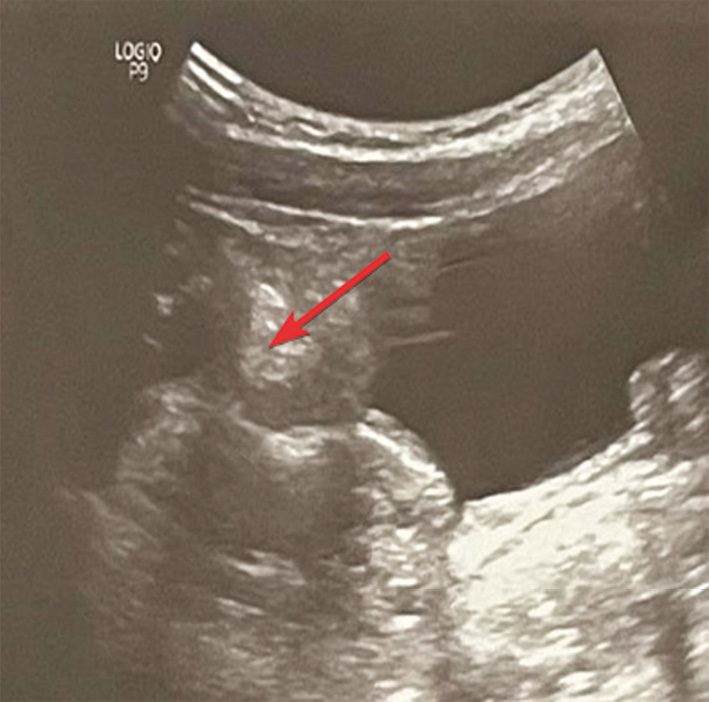

Рис. 2. Лапароскопия. Перекрут правого яичника на 720° на уровне отхождения маточной трубы. 1 — правый яичник; 2 — место перекрута правого яичника

Fig. 2. Diagnostic laparoscopy. Torsion of the right ovary by 720º at the level of the fallopian tube. 1 — right ovary; 2 — place of torsion of the right ovary

На уровне отхождения маточной трубы обнаружен перекрут на 720°. Левый яичник расположен в типичном месте, визуально не изменен. Червеобразный отросток вторично изменен: инъецирован у верхушки, верхушка ригидная, запаян у основания плоскостными спайками, наблюдаются воспалительные изменения серозной оболочки. Выполнена деторсия правого яичника, после которой через 10 мин восстановилось кровоснабжение. Ввиду макроскопических изменений червеобразного отростка проведена аппендэктомия. При патоморфологическом исследовании: серозная оболочка отечная с диффузной лейкоцитарной инфильтрацией, сосуды полнокровные с лейкоцитами в просвете сосудов. Слизистая оболочка без воспалительных изменений. Заключение: вторичный аппендицит.